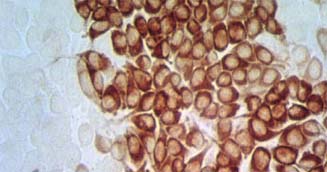

Galería Fotográfica - Peste Porcina Clásica

Aislamiento